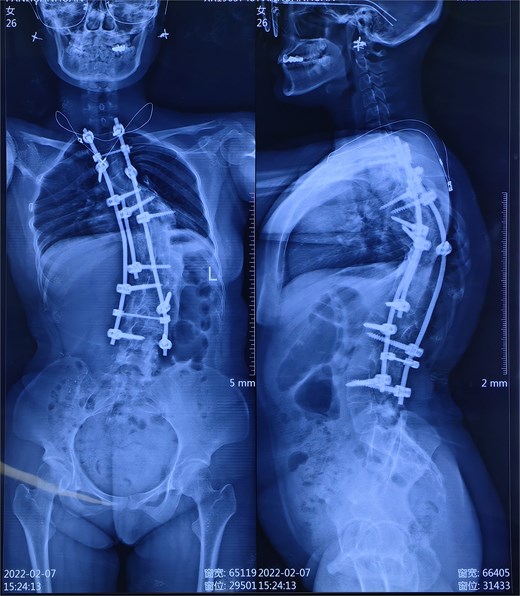

A 28-year-old female at 37 weeks and 3 days of gestation presented for elective cesarean section. Her medical history included scoliosis corrected via thoracolumbar instrumentation in 2011 and moyamoya disease treated with left superficial temporal artery–middle cerebral artery bypass surgery in December 2022. Residual scoliosis, spinal hardware, and surgical scarring obscured surface landmarks. Physical examination revealed persistent thoracolumbar curvature (Cobb angle not quantified), poor alignment of spinous processes, and scarring over the surgical site (Fig. 1). Neurological evaluation showed no deficits. Preoperative lumbar spine radiographs confirmed residual scoliosis and instrument placement (Fig. 2). Magnetic resonance angiography demonstrated stable moyamoya vasculature without active stenosis.

Radiographs showing thoracolumbar instrumentation and residual scoliosis.